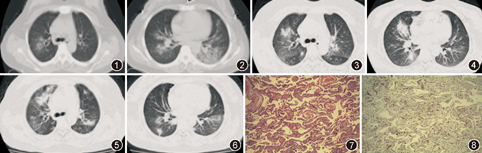

患者女,47岁,家庭妇女。因"反复咯血4年,伴胸闷3年,再发1 d"于2011年2月25日入院。患者2007年2月起无明显诱因下出现反复咯血,以痰中带血为主,偶咯2~3口鲜血,在当地结核病防治所拟诊"肺结核",给予正规抗结核治疗1年,咯血无好转。2008年7月21日及8月13日先后2次因反复咯血伴胸闷,于我科住院治疗。2008年7月21日胸部CT示双肺浸润影(图1,图2)。拟诊"肺部感染"给予"头孢他啶、巴曲酶"等治疗后,咯血、胸闷症状好转出院。出院2 d后再发咯血伴胸闷,日咯血量约5~10 ml,再次入院。复查胸部CT见双肺出现新的浸润性病灶(图3,图4)。支气管镜检查可见支气管腔内有陈旧性血迹,经支气管镜下肺活检提示肺泡腔内有含铁血黄素细胞,肺泡组织呈慢性炎症性改变。拟诊"外源性过敏性肺泡炎?",给予甲泼尼龙40 mg/d,治疗5 d咯血胸闷好转,复查胸部CT,双肺浸润影部分吸收。出院后继续口服糖皮质激素,咯血、胸闷症状仍反复发生,就诊多个医院,给予糖皮质激素治疗达2年,伊曲康唑口服液治疗4个月,症状无好转。2011年2月25日,患者因再次咯血、胸闷入院。此次咯血量无明显增多,每日约5~10 ml,呈鲜红色,伴活动后胸闷。患者自发病来,意识清楚,精神较差,食欲睡眠尚可,大小便正常,体重无下降。患者既往有糖尿病史7年,口服阿卡波糖片治疗,血糖控制较理想。有高血压病史2年,长期口服厄贝沙坦片,血压控制在120/80 mm Hg(1 mm Hg=0.133 kPa)左右。有克拉霉素过敏史。否认饲养鸽子、宠物等,否认肝炎等传染病史。否认家族遗传性疾病史。

入院后实验室检查:血常规示白细胞为7.40×109/L,中性粒细胞为0.7,嗜酸粒细胞为0.02,血红蛋白为117 g/L,血小板为177×109/L。ESR为50 mm/1 h,C反应蛋白为74.20 mg/L,尿常规、便常规正常,IgE为2.49 IU/ml,D-二聚体为2.81 mg/L,B型尿钠肽(BNP)正常,余凝血常规、生化、肿瘤系列、甲状腺功能、免疫球蛋白、补体、抗核抗体系列、抗中性粒细胞胞质抗体(ANCA)系列及类风湿因子等均正常,血气分析正常。肺功能检查示轻度限制性通气功能障碍,弥散功能轻度下降。痰细菌、真菌培养阴性,痰涂片找抗酸杆菌3次均阴性。肺吸虫皮试阴性。腹部B超未见异常。双下肢深静脉B超未见异常。心电图正常。心脏超声提示:左心室顺应性下降,肺动脉压力正常。胸部CT提示双肺散在浸润灶(图5,图6)。

董磊(病理科):肺毛细血管瘤是一种毛细血管增生性疾病,其病理特征为薄壁增生的毛细血管浸润至肺实质、肺间质、支气管、肺血管结构和胸膜,增生的毛细血管易出血,可致肺泡腔内出现含铁血黄素细胞[1]。本例患者的病理表现除灶区间质纤维化、增生纤维突入肺泡腔外,大部分肺泡结构正常,肺泡腔可见出血,肺泡上皮细胞未见明显异常;肺泡间隔增宽,间隔内可见扩张、充血的毛细血管,内衬扁平血管内皮。免疫组织化学标记Ⅷ因子相关抗原见肺泡间隔多量Ⅷ因子相关抗原阳性(棕色)的毛细血管分布,病变处支气管及附近胸膜亦可见环周的毛细血管增生;毛细血管瘤性增生区呈不规则片状分布,与周围正常肺组织分界不清(图7,图8)。因我院对肺毛细血管瘤的病理诊断经验不足,HE染色病理组织见局灶的机化性肺炎的表现,而误诊为COP。